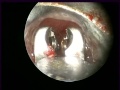

Bronxoskopiya Yad cismin cixarilmasi. Dr. Fuad Huseynov

Sağ aksesuar Bronxa guide. Uşaq cərrahı Dr.Fuad Hüseynov